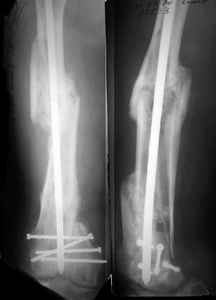

I presented a series of ~25 such cases at EuroTrauma'2004. Many cases were discussed here. I attach am example. Look also recent cases at http://www.hwbf.org/hwb/conf/alex58/scfx.htm,

http://www.hwbf.org/hwb/conf/alex63/alex63.htm

I do realize that you are master surgeon, and congratulations on another excellent, spectacular case (result), but,

- Your last posted case: how is possible to have secure fixation with applied construct without additional casting, bracing or Ilizarov?

THX, initial images are

1,

2.

KEMMD> - Your last posted case: how is possible to have secure fixation with

KEMMD> applied construct without additional casting, bracing or Ilizarov?

At that moment we had in stock only the 10 mm solid nails so of course there was no idea about early weight bearing. But it was quite enough for early knee ROM excersises (see attached). Two locking screws through the distal block provided that.